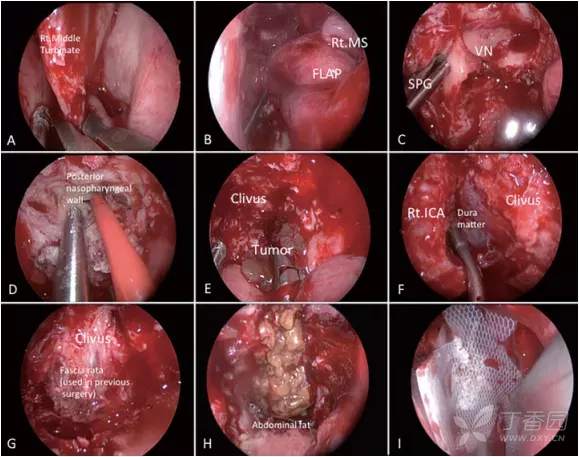

图2:术中30度内窥镜下的术中照片。(A和B)左中鼻甲切除术后取鼻中隔皮瓣,皮瓣保存在左上颌窦内。(C)牺牲右翼管神经,转位蝶腭神经节,扩大手术通道。(D) 切开鼻咽后壁,以暴露枢椎齿状突。(E) 在斜坡钻孔后,将位于硬膜外的肿瘤切除。(F) 显露颈内动脉前、中侧面后,使用带角度器械切除位于颈内动脉后部和斜坡之间的肿瘤。(G)为避免脑脊液漏及纤维面硬脑膜内剥离,仅切除硬脑膜外的肿瘤。在既往的内镜经鼻内入路中使用的阔筋膜保护完好。(H) 移植腹部脂肪和使用胶原蛋白海绵水密缝合硬膜,关闭硬膜。(I)使用鼻中隔皮瓣重建鼻中隔,并用硅胶片固定。

该阶段手术后,X女士没有出现新的神经功能缺损、颅神经功能障碍或脑脊液渗漏,正如预期的那样。

图3,鼻内镜下肿瘤切除术后影像学检查(第一阶段术后)。显示脑干充分减压,正中中线部分肿瘤切除,其他在枢椎齿状突、C1侧方和硬膜内残留肿瘤等待第二阶段开颅手术切除(A-D)(绿色箭头)。